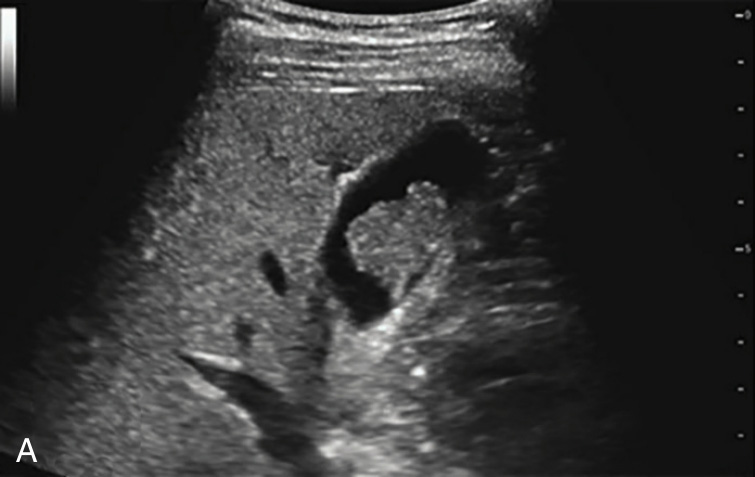

图2-3-2 腺瘤样性息肉常规超声图像

A.胆囊体部单个结节状中等回声,内部回声欠均匀;B.病灶内部分支状血流信号

胆固醇性息肉多呈高回声,较小者可呈强回声伴彗星尾征(图2-3-1);腺瘤性息肉多呈等回声(图2-3-2);炎症性息肉少见,多合并胆囊炎或胆石症。胆囊息肉一般后方无声影,不随体位改变而移动。

对于较小的息肉,CDFI一般无明显血流显示。较大的息肉或腺瘤性息肉,CDFI可显示点状或从底部进入的细条状动脉血流。